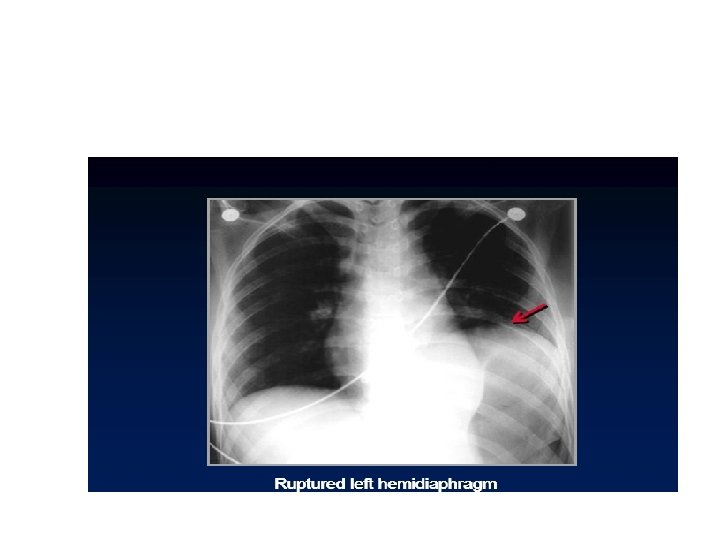

Continuous diaphragm sign